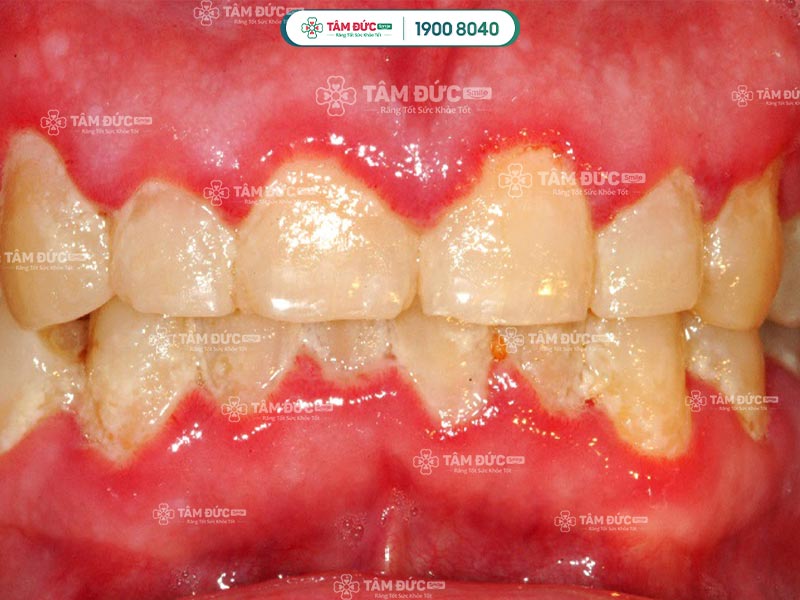

Viêm lợi là tình trạng lợi răng bị sưng tấy, lợi chuyển thành màu đỏ và gây cảm giác đau. Viêm lợi vừa gây ảnh hưởng sức khỏe, vừa làm Quý khách giảm đi cảm giác ngon miệng và làm tăng nguy cơ bị mất răng vĩnh viễn.

Những mảng bám tích tụ lâu ngày ở viền lợi bị vôi hoá, trở nên cứng dần tạo thành cao răng. Đây là nơi tập hợp của nhiều vi khuẩn có hại, chúng tấn công lợi gây nên nhiễm trùng, viêm sưng.

Viêm nha chu: Đây là giai đoạn sau của viêm lợi. Lúc này Quý khách cảm thấy vùng lợi rất đau, sưng và bị chảy máu. Hơi thở của Quý khách nặng mùi hơn, răng bị thưa và có thể chảy mủ.